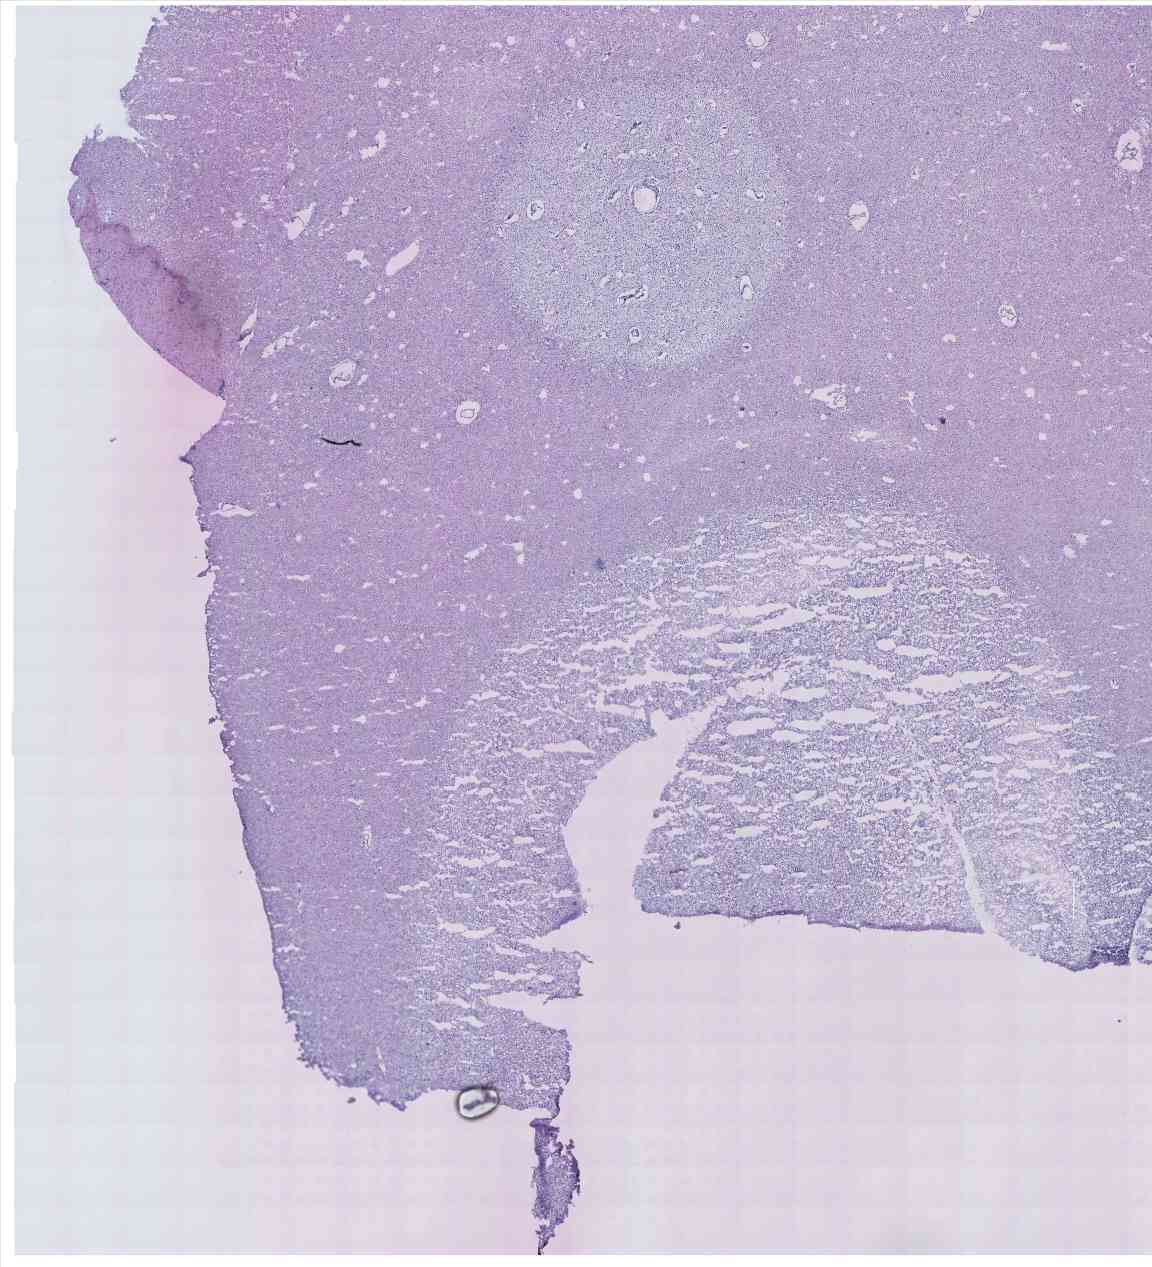

Chip 061 Well E1